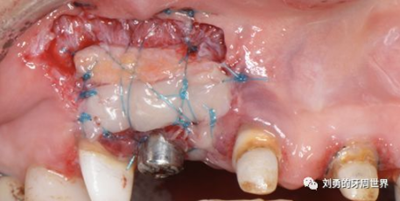

下面這個(gè)是我使用國(guó)產(chǎn)的替代品的病例:

但是該方法對(duì)于縫合技術(shù)要求較高,因此本人嘗試了新的方法,膜釘固定:

該方法操作簡(jiǎn)單,但是需要擇期局麻下拆除膜釘。